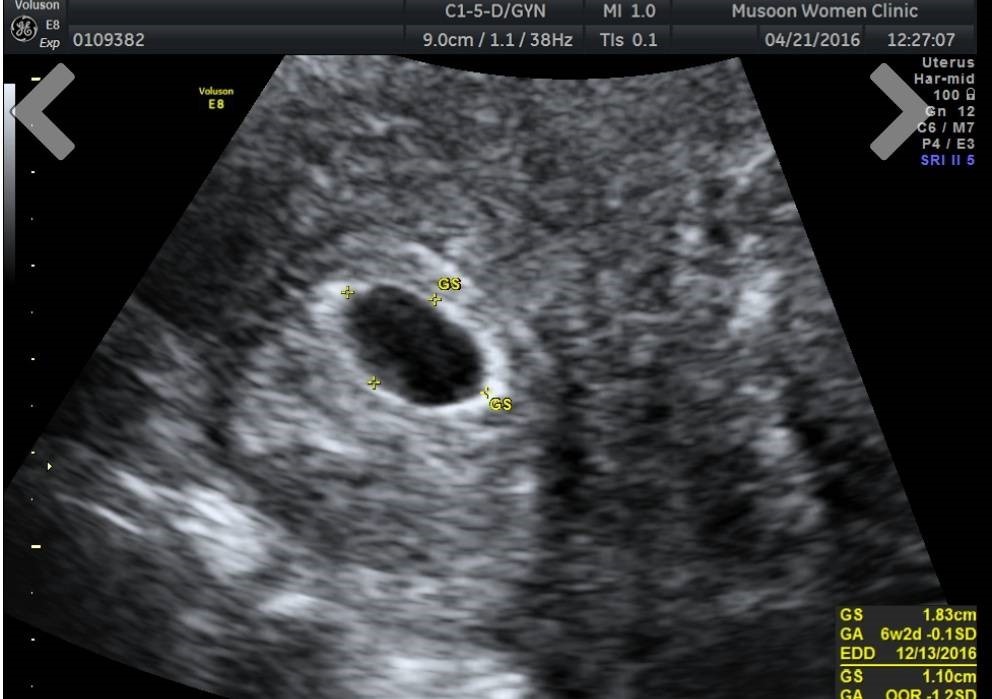

等到開始覺得事情有些不妙,決定要正視這個問題的時後,自己早已過了適孕期(簡單來説就是高齡媽媽!),想想,這也没有什好緊張的,在現代的社會中,醫學這麼發達,高齡產婦也不是什麼新聞,不怕!不怕!抱著姑且一試的心態去看醫生,不看還好,這一看,就直被判定極刑除非子宮來個大掃除,不然根本不用想。

但是判刑總有上訴的機會吧?!換個醫生再來看看,總會想到好辦法,走訪了幾位名醫,直到婦產科權威的宣判—子宮肌瘤,子宮腺瘤,子宮内膜異位,再加上老化的卵子和超高齡…集所有不利於懷孕的問題於一身,懷孕機率幾近為零(連人工受孕這筆錢都可以省下來,因為就没有著床的機會與位置),直到這個時後我們才深深明白,未來的路上,我們註定只能兩人手牽手一起走,不會有"地表最強小三或者小王"的介入…!!

眼看大勢已去,我們也不再抱持著任何期望,只能繼續寄情於工作;就在一切看似無望的某一天回家的路上,不知道哪根筋不對,突然想到去買了一個結婚十幾年從來都沒在家裡出現的東西—驗孕棒,更不可思議的是,它竟然顯出了奇蹟的兩條線,讓我一度以為是自已眼睛”業障重"。接下來,就是看到手忙腳亂的兩個人,匆匆忙忙的往婦産科衝。

但是現實生活畢竟不是童話故事,不是"王子和公主從此過著幸福快樂的日子"這樣簡單的結束! 看來,我們家的小天使可是費盡千辛萬苦・終於才在茫茫人海中找到媽咪;而為了能夠來到媽咪的身邊,又得在那片充滿岩石的沙漠荒野,尋找那針頭般的小小落腳處(著床),但這個糟到不能再糟完全不利於寶寶居住的環境,要生存下去得要有葉問般一個打十個的精力,所以,從"知"的那一天起,即開始了最刺激的十個…,如同是十年抗戰,喔! 不! 是十個月的抗戰生活。